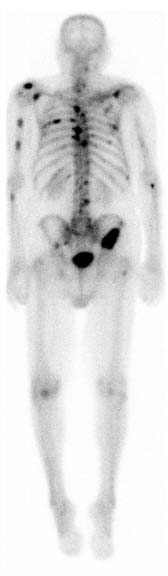

Gamagrama óseo con múltiples metástasis a arcos costales y columna

Gamagrama óseo con metástasis múltiples por cáncer de próstata